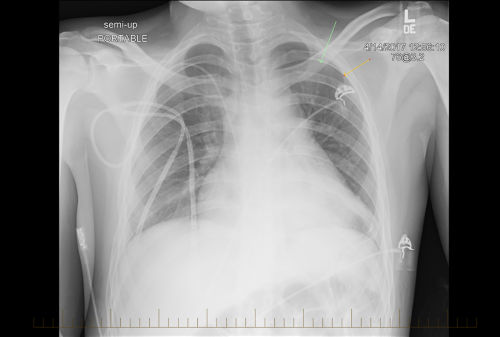

Chest X-ray of pediatric non-Hodgkin lymphoma patient shows evidence of disease

X-ray of pediatric non-Hodgkin lymphoma with evidence of disease.